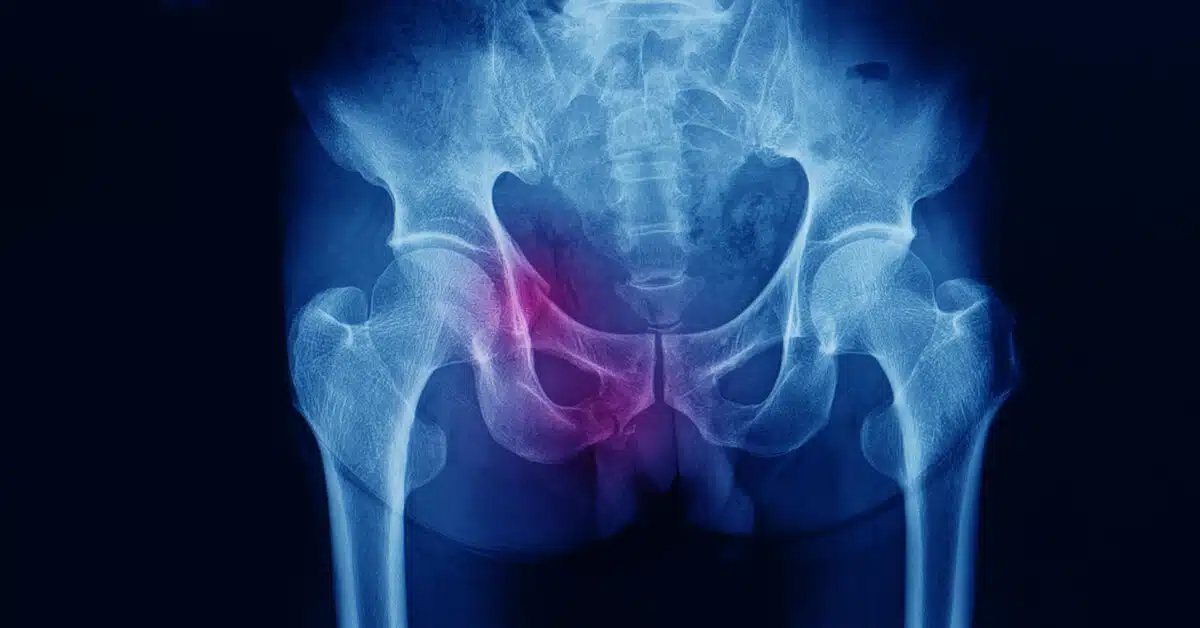

ينتج عن كسر في مفصل الحوض ألم شديد يمنع المريض من تحريك مفصل الورك بشكل طبيعي، في حالات الكسر الحاد تترافق الإصابة مع تلف في أحد الأعضاء الداخلية أو تمزق في الأوعية الدموية، مما يؤدي إلى نزيف داخلي قد يقلل من تدفق الدم في الجسم.

يتم تشخيص الكسر عادة باستخدام تصوير الأشعة السينية للحوض لتحديد تفاصيل الكسر بدقة، يطلب من الطبيب إجراء فحص بالأشعة المقطعية، حيث يجري الدكتور عمرو أمل أفضل دكتور عظام في مصر تقييم شامل للأعضاء الداخلية والأوعية الدموية والأعصاب المحيطة للتأكد من عدم وجود إصابات إضافية مرتبطة بالكسر.